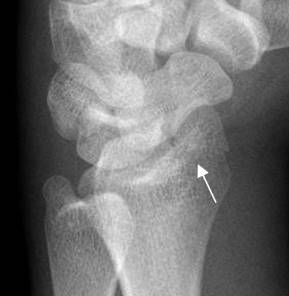

Fig 206. Fractura de Smith.

A y B: Rx lateral de muñeca. Fractura de Smith, con desplazamiento anterior del fragmento distal del radio.